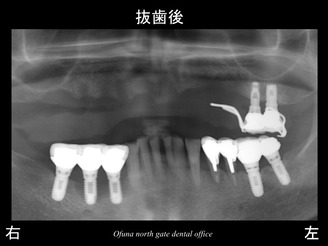

以下が抜歯後です。

抜歯後は暫くの間 義歯(入れ歯)になります。

このようなケースの場合、抜歯前に型を取ります。

そして、抜歯と同時に義歯を装着しますので、歯がないという期間は1日もありません。